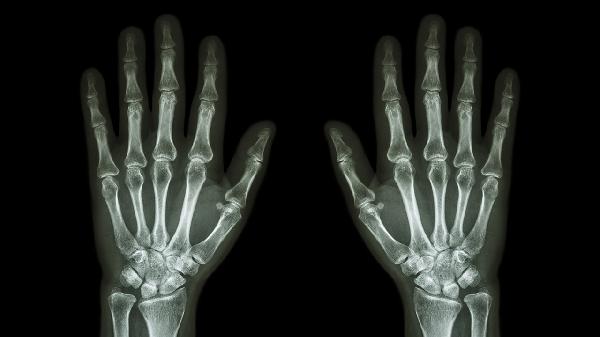

关节软骨磨损后骨赘增生形成骨性硬结,多伴随晨僵和活动弹响。X线可见关节间隙狭窄,治疗采用玻璃酸钠注射联合氨基葡萄糖口服,晚期需关节成形术。